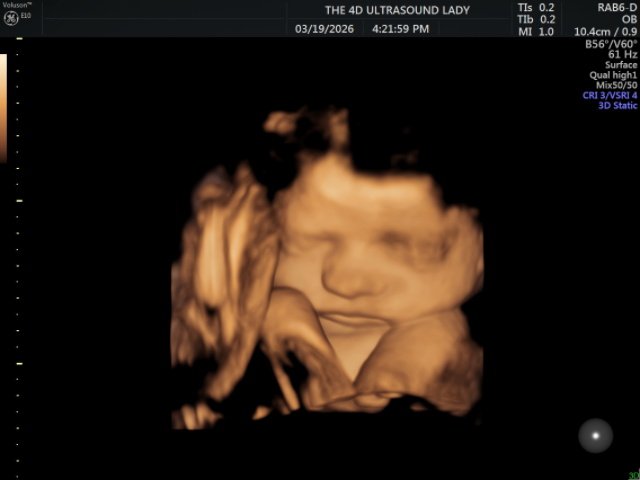

This month, our transfer process looked a little different, which caused a portion of our support to be delayed. While it should arrive next month, this has made the current month especially challenging. As we prepare for the baby’s arrival, there are several additional expenses, which makes this season feel even tighter. We would greatly appreciate prayer for wisdom as we make financial decisions and seek to be good stewards of what we have. We are also trusting the Lord for provision, especially with the upcoming costs of the birth, as well as the paperwork and embassy visits required for Presley’s birth abroad and passport. - My Birth

Please pray for a healthy delivery for both mom and baby. Our hope is for a smooth and natural birth, but above all, we are praying for safety and health for both of us. - Energy for Both of Us